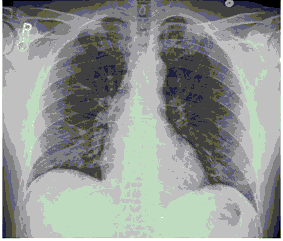

Стандартная РГ имеет низкую чувствительность в выявлении начальных изменений в первые дни заболевания и не может применяться для ранней диагностики. Информативность РГ повышается с увеличением длительности течения пневмонии. Рентгенография с использованием передвижных (палатных) аппаратов является основным методом лучевой диагностики патологии ОГК в отделениях реанимации и интенсивной терапии (ОРИТ). Применение передвижного (палатного) аппарата оправдано и для проведения обычных РГ исследований в рентгеновском кабинете. В стационарных условиях относительным преимуществом РГ в сравнении с КТ являются большая пропускная способность. Метод позволяет уверенно выявлять тяжелые формы пневмоний и отек легких различной природы, которые требуют госпитализации, в том числе направления в ОРИТ.

КТ имеет высокую чувствительность в выявлении изменений в легких, характерных для COVID-19. Применение КТ целесообразно для первичной оценки состояния ОГК у пациентов с тяжелыми прогрессирующими формами заболевания, а также для дифференциальной диагностики выявленных изменений и оценки динамики процесса. КТ позволяет выявить характерные изменения в легких у пациентов с COVID-19 еще до появления положительных лабораторных тестов на инфекцию с помощью МАНК. В то же время, КТ выявляет изменения легких у значительного числа пациентов с бессимптомной и легкой формами заболевания, которым не требуется госпитализация. Результаты КТ в этих случаях не влияют на тактику лечения и прогноз заболевания при наличии лабораторного подтверждения COVID-19. Поэтому массовое применение КТ для скрининга асимптомных и легких форм болезни не рекомендуется.